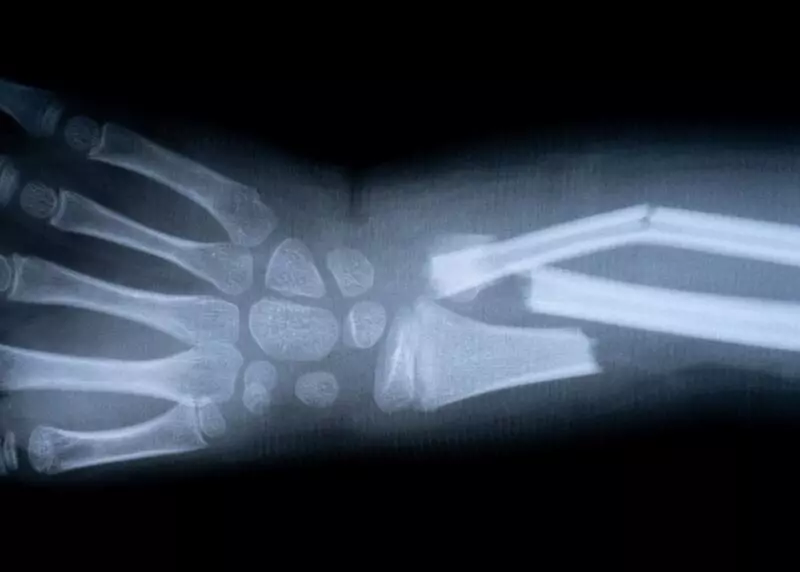

Для точного определения типа перелома проводится рентген в двух проекциях. Это позволяет врачу увидеть не только наличие повреждения, но и его характер: поперечный, косой, спиральный или винтовидный. От этого зависит выбор тактики лечения — консервативной или хирургической.

Рентген в двух проекциях — золотой стандарт при подозрении на перелом. Он показывает: есть ли линия перелома; насколько смещены отломки; затронут ли сустав.

В сложных случаях, например, при переломах таза, позвоночника или мелких костей стопы, может потребоваться компьютерная томография (КТ). Она дает трехмерное изображение, позволяющее увидеть даже мельчайшие фрагменты и спланировать операцию с максимальной точностью.